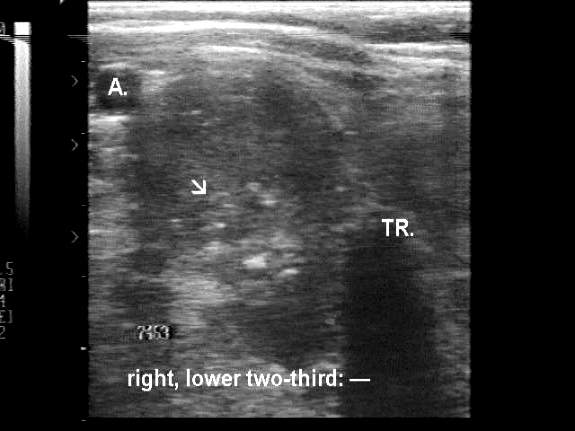

Ultrasonography revealed a multinodular goiter. Hypoechogenic nodules were found in both lobes. They displayed microcalcifications and larger, cotton-like hyperechogenic patches without dorsal acoustic shadow. These patches correspond to amyloid. (The patient was evaluated in 1996, therefore the sonographic images are technically out of date. Nevertheless, these are already edifying.)

1. The sonographic pattern is very specific for medullary cancer: cotton-like hyperechogenic patches without acoustic shadow occupying more than 50% of a hypoechogenic nodule